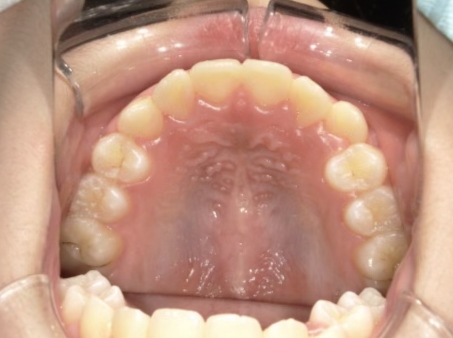

| カウンセリング・診断結果 | 前歯の生え変わり時期に来院されました。(写真①) 乳歯列期に受け口の既往があり切端咬合になりそうなため、受け口に対する矯正治療の考え方と対処法、当院のコンセプトを説明したところ治療を希望されたので診断を行いました。 診断の結果、上顎骨に対し下顎骨が長く、骨格的な構造も下顎突出型反対咬合(下顎骨が適切な位置よりも前に出ているタイプの受け口)と分かりました。 顔立ちは、中顔面が引っ込んだように見えるコンケーブに移行中です。 機能的な問題として低位舌があるため受け口の悪化が考えられることも説明し、以下の治療を提案しました。 |

| 行ったご提案・診断内容 | 成長期に行う治療と咬合治療をご提案 成長期受け口用モノブロック装置(筋機能的装置)を*MFTと併行して先行し、小学2年生以降で、拡大・前歯の調整へ移行し、咬合治療は受け口悪化予防と咬合の構築効果がある咬合治療用モノブロック装置(筋機能的咬合誘導装置)へ移行する提案をしました。 成長期治療(成長時期にお口の環境を整える治療) 咬合治療 経過観察 |